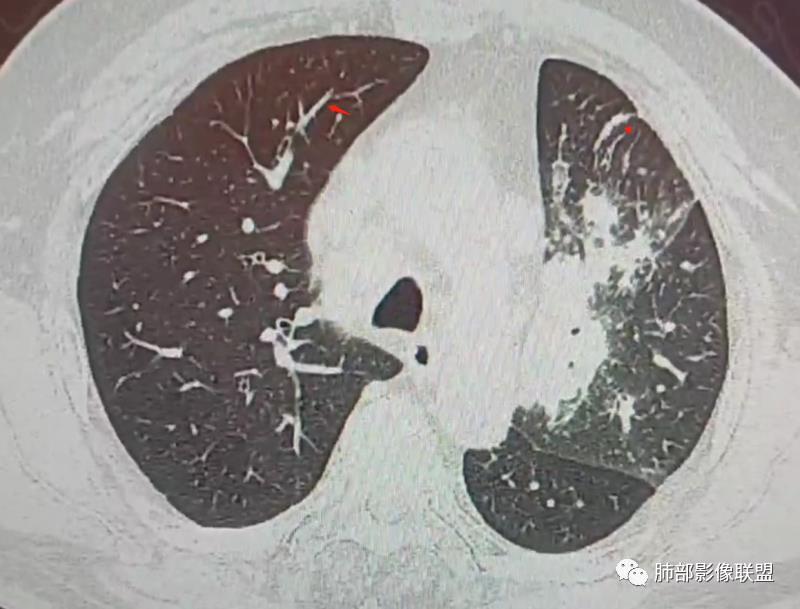

南边:这些是中轴间质增厚?树芽征?

Coke with ice:潘老师,这里是小叶间隔吧?串珠样的。

南边:是的。

南边:尖后段弥漫小叶间隔,中轴间质增厚,部分有结节感,大家考虑啥。

Coke with ice:我觉得是典型的癌淋,较大范围的,比如叶分布,甚至是整个单侧肺,单侧的肺小叶间隔增厚,极大概率是癌淋,另外一个疾病谱就是负压性肺水肿。

Coke with ice:这里有点像原发。隆突下也有大淋巴结。

三、影像表现:左肺上叶多发片状高密度影,散在,边缘模糊,支气管壁稍增厚,中轴间质、小叶间隔增厚、有结节感,左肺上叶前段病灶可见胸膜增厚,部分小支气管不能分辨;右肺上叶后段混合磨玻璃结节,边界清,邻近胸膜凹陷;纵膈淋巴结肿大;心包增厚;左侧少量胸水。此外,扫及右侧胸腔内甲状腺肿;左侧肩胛骨旁肌群内脂肪瘤。

四、综合分析:老年男性,以咳嗽咳痰为主要临床表现,无发热,白细胞正常,影像表现为左肺上叶片影,前段结节影、胸膜增厚、部分小支气管不能分辨。左肺上叶中轴间质增厚、小叶间隔增厚、结节感,肺门纵隔见肿大淋巴结,尽管肺部病病灶边缘特征不典型,但高度疑及癌性淋巴管炎这一“次生灾害”却具有相当重要提示意义,而肺癌中最常伴癌淋的就包括腺癌。右肺上叶后段混合磨玻璃结节,边界清楚,张力明显,具有一定特征性,高度指向浸润性腺癌。这对于左肺病灶具有一定程度“助攻”效应。总体而言,本例左肺病灶的诊断关键点在于判断出癌性淋巴管炎。癌性淋巴管炎的结节在外围间质多见,小叶间隔可呈串珠状、结节状增厚,由于出血及水肿,小叶间隔增厚较明显,或呈不规则增厚。有的肺小叶呈多角状阵列。常合并胸水。

肺癌性淋巴管炎(PLC)是肺内、外肿瘤肺转移的一种特殊类型,以 转移癌细胞在淋巴管内弥漫性生长为特征,占肺内转移瘤的6.8%。癌 细胞可播散至肺淋巴管及血管,最终因呼吸衰竭和肺源性心脏病而导致病死亡。临床症状主要为干咳、憋气、体重减轻及低氧血症。本病预后极差,50%~85%的患者生存期3~6个月,临床诊断较困难,常误诊为其它肺间质性病变。 PLC的主要CT征像当中肺纹理异常改变最常见,肺纹理不规则增多、增粗并多发微小结节状更形象解释癌细胞在淋巴管内生长成结节及周围间质增生,导致淋巴管通道堵塞,远处淋巴液回流受阻,通过其它细小交通回流,从而导致肺纹理增粗增多,是PLC较有特征性CT征象,其它疾病所导致的肺纹理增多增粗一般较规则,可为粗细不均或受牵拉变形却极少出现结节状增粗并呈串珠状排列。小叶间隔不规则增厚并多发小结节也是因为小叶间隔淋巴管癌细胞生长及淋巴管通道受阻扩张所致,虽然小叶间隔结节状增粗,但小叶结构不变形是PLC较为特征的CT表现,肺纤维化、 肺水肿、肺胶原病及结节病等肺间质性病变中较少见小叶间隔结节状增粗,而且它们一般导致肺小叶结构变形。肺小叶内间质增生及(或)核心小结节无明显特异性,其表现与特发性肺纤维化、 尘肺及结缔组织病及其它可导致肺间质性纤维化疾病的小叶内间质增厚相类似。PLC导致的胸膜增厚也有一定特征,一般累及胸膜范围较广,程度轻,密度较淡, 部分呈花边样改变,以叶间胸膜较常见,绝大部分病例叶间胸膜受累呈轻度增厚并沿表面排列多发微小结节,伴随PLC其它征象,未见单独存在。肺内结节及 (或)小斑片状实变影无特异性, 与肺结核、炎症、肺血行转移瘤及类风湿等结缔组织病的肺部表现相似,也可能为合并血行转移及肺部感染。纵膈及肺门淋巴结肿大、胸腔及心包积液均无特异性,曾有文献报道,单侧叶间裂积液对PLC的诊断有相对特异性, 因单侧的叶间裂积液主要是由于胸膜下淋巴管堵塞,淋巴回流受 阻所致,可提示PLC的存在。

综合上述,肺纹理不规则增粗并多发微小结节、肺小叶间隔不规则增厚并多发微小结节、轻度增厚的胸膜并多发微小结节对诊断PLC具有重要意义,三者征像同时存在时,结合肿瘤病史及临床症状, 基本可以明确诊断PLC。